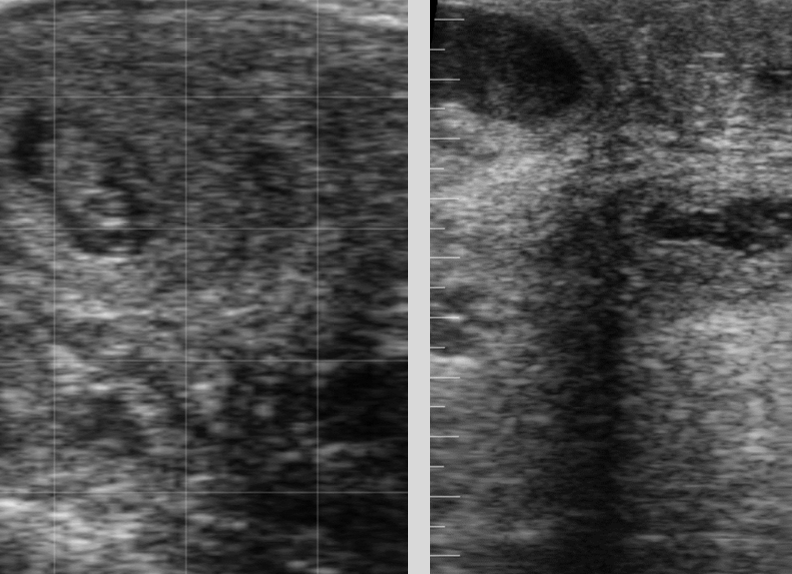

how is pyometra diagnosed?

palpation and U/S

-no fetus

-no placentomes

-visualize flocculant material